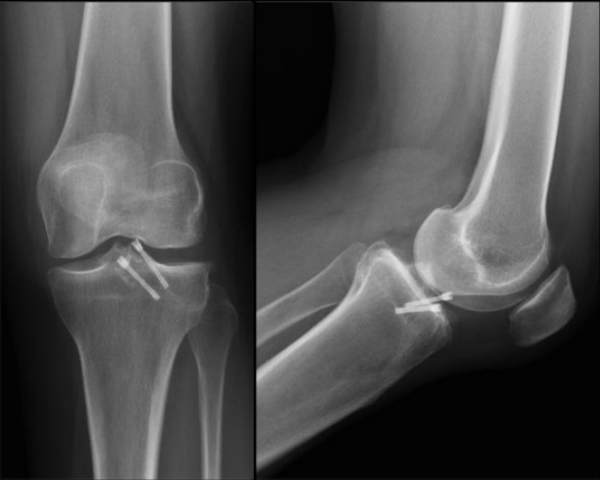

Se constató consolidación radiográfica de la avulsión en todos los casos (fig. 3).

Figura 3: Radiografía de rodilla izquierda frente y perfil. Consolidación de la fractura por avulsión de espina tibial tratada con dos tornillos Herbert anterógrados.